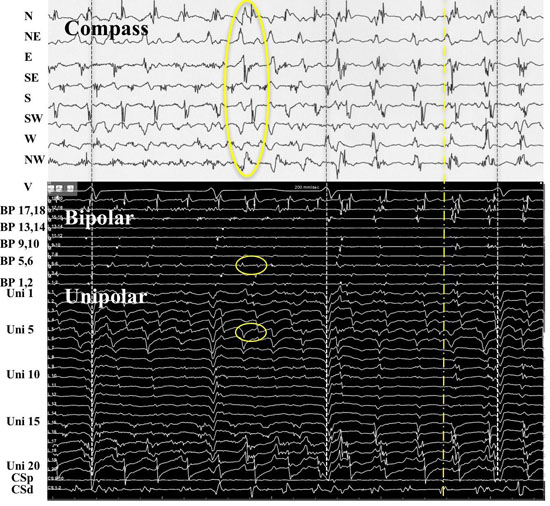

In patient #18, at LA position #7, rotational activity was noted to be slowly transitioning from the perimeter with DPs on all 3 forms of recordings (compass, narrow-adjacent bipolar, and unipolar, [Figure 8] to a position outside of the compass, generating a PW [Figure 8C]. The PW, identified by the vertical yellow dashed line on the right, shows a wavefront that has earliest activation at electrodes 5,6 at the NE compass point. Two cycles earlier than the yellow line, the largest gap in time is seen on unipolar 6. Note the drop of ½ of the signals from electrodes 6 through 20. This position site as seen in[Figure 8AandFigure 8D], was incorporated within the ablation line that circumnavigated the left PVs. Isolation was achieved, Afib persisted. Just prior to completion of the right PV isolation line, AF terminated. This patient has remained arrhythmia free for 22 months. Our simulation of the activation sequence of a rotor is taken further and breaches a line of electrodes or a perimeter of electrodes around a circular catheter (Movie 2 and Movie 3). This slow-motion identifies an expected pattern of activity that would be specific to a rotor or any rotational mechanisms that moves completely to the other side of the recording line. If a rotor close to the line of electrodes moves along a path towards the midpoint of 2 electrodes, then relative Doppler compression of wavefronts are expected on the electrode receiving the forward moving waves that are parallel to this path. A relative Doppler expansion of wavefronts are expected on the second electrode that is on the opposite side of the rotor. This second electrode receives the backward moving wavefronts relative to the precession direction. At this moment of transition a PW with mostly vertical alignment of activation signals becomes slanted or sequential in alignment where head-meets-tail. That transition, that breach, occurs at the site between the 2 electrodes that exhibit maximal Doppler compression and maximal expansion of wavefronts. This occurs at the moment that activation sequence reverses in direction (movie2 and movie3). Whether precession occurs past a line of electrodes, or along the perimeter of a circle, that transition pattern of Doppler compression and expansion is the same. The progressive delay in activation at the 2nd electrode along with the simultaneous changes in all the other electrodes along the line, results in a unique pattern of activation change that we label as the ½ cycle drop-off. This position and moment in time of sequence reversal, puts a very specific location of the center of rotation. The ½ cycle drop-off would be unique to a rotor or a microreentrant mechanism, since it requires the entire circular path to have crossed the line between the 2 electrodes.

Figure 8. Rotational mechanism at perimeter of circular catheter. A. 3-D anatomical map with transparent position of circular catheter placed at LA site 7 in patient #18. B. Top 2 tracings show surface leads I and V1. Next 10 tracings show narrow-adjacent bipolar electrode recordings around circular catheter, then unipolar electrodes followed by coronary sinus (CS) proximal (p) and distal (d). The last trace shows recording from CS catheter. Yellow circle shows position of electrode 5 at site of DPs as seen throughout recording of bipolar pair (5,6). C. Simultaneous recordings at LA site #7 from top: compass map (top 8 recordings), V1 surface recording used to synchronize all recordings with grey-white dashed lines, middle: narrow-adjacent bipolar (middle BP pair 10 recordings), unipolar (bottom Uni 20 recordings) around catheter and then coronary sinus (CS) proximal (p) and distal (d). The yellow circles show simultaneous DPs in unipolar 5, narrow-adjacent bipolar 5,6, and throughout compass recordings. The yellow dashed line shows the rotational mechanism precessing out away from perimeter of circular catheter as DP pattern switched to PW on compass, bipolar, and unipolar recordings, while the sequential activation gives way to a more vertical alignment. Note that location is corroborated by the largest amplitude, earliest positive deflection occurs at NE – E direction which is exactly where electrode pairs (5,6) reside. D. Superimposed ablation lesions compared to location of relatively stationary rotational mechanism. Electrode 5 is well within the lesion set to isolate the left PVs.

Figure 8B.

Recordings from patient #21 at position 9 [Figure 9AandFigure 9B] shows simultaneous compass, narrow-adjacent bipolar and unipolar recordings of a transition from a PW to DP and then back to PW. At the moment of wavefront pattern transition occurs in compass mode, the unipolar activation pattern shows the Doppler compression and expansion at poles 12 and 11 respectively, while the same bipolar pair (11,12) exhibit DPs. The ½ cycle drop-off occurs above electrode 10. The opposite transition occurs with precession out from the circle. This pattern repeated a total of 5 times during the 1 minute of recording.

Figure 9. A rotor precessing in and out of a circular perimeter of electrodes. Simultaneous methods of recordings were performed at LA site #9 from patient # 21. From top: Surface lead V1, narrow-adjacent bipolar pair 1,2 and 3,4, compass recordings (next 8 recordings), narrow-adjacent bipolar pairing 1-20 electrodes, unipolar recordings 1-20, and coronary sinus (CS) tracings proximal (p) to distal (d). Initial wavefront pattern is a PW on compass recordings (black vertical oval) with fairly vertical alignment of bipolar and unipolar recordings. As rotor precesses passed the perimeter, alternating DPs (gold arrows) develop throughout compass recordings while a sequential alignment (slanted white circles), head-meets-tail of narrow-adjacent bipolar and unipolar recordings. A ½ cycle drop off occurs between electrodes 11 and 12. A Doppler compression of wavefronts occur at electrode 12, while there is a Doppler expansion at electrode 11. White dots show the moment that the 1/2 cycle drop off occurs when the vertical alignment switches to sequential alignment and reversal of activation sequence. The narrow-adjacent bipolar recording shows a DP as the rotor passes between the 2 electrodes. The right-hand portion of the figure shows the opposite movement of the rotor passing between electrode 11 and 12. The rotor continues to spin with the same direction. Sequential activation with a slanted head-meets-tail alignment are identified by white slanted circles. As expected the rotor precessing in the opposite direction of between the same electrode pair exhibits a Doppler compression of wavefronts at electrode number 11 while electrode 12 receives a Doppler expansion of wavefronts (white dots). A DP appears at the narrow adjacent bipolar recording of 11,12 at the moment of ½ cycle drop off occurs and when the PW pattern appears on the compass recordings (black vertical oval). Grey to white dashed lines synchronize unipolars to compass recordings.